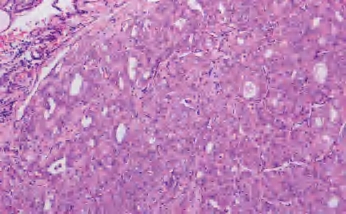

3.镜下 为复杂分支状乳头,含纤维血管轴心,细胞拥挤,核增大,呈卵圆形、沙砾体,表面被以单层柱状上皮,半数以上核呈毛玻璃样,有核沟,核内假包涵体(图3-40至图3-43)。

图3-40 甲状腺乳头状癌

图3-41 甲状腺乳头状癌